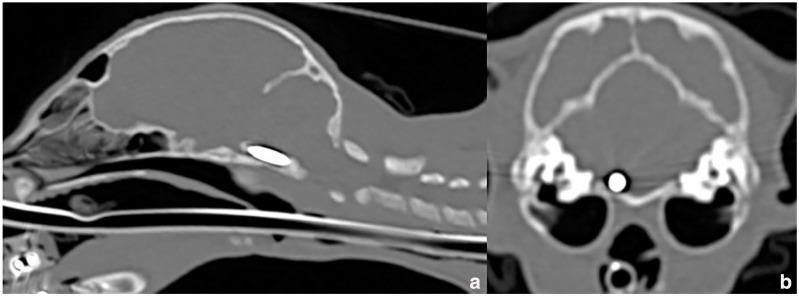

Case summary: A 2-month-old kitten was presented for ataxia and depressed mental status after implantation of a pet identification microchip. Radiographs were taken immediately by the referring veterinarian and showed a longitudinal metallic foreign body (electronic microchip) within the cervical vertebral canal at the craniocervical junction. A CT examination 2 days after the incident showed cranial migration of the microchip ventrally to the caudal brainstem. Ventral basioccipital craniectomy was immediately performed to retrieve the microchip by a ventral approach to the caudal brainstem. Postoperative recovery was uneventful and the cat was discharged 2 days later. At the 2-week follow-up, neurological examination of the cat was normal. No long-term complications were reported.

Relevance and novel information: This case report describes the intradural migration of a microchip and surgical removal via ventral basioccipital craniectomy.